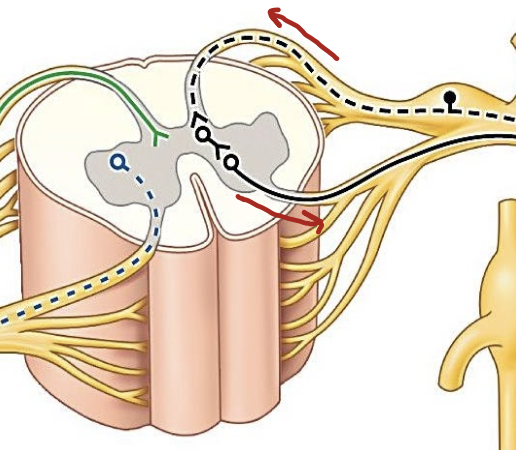

The spinal cord is composed of what?

White matter (Axons) and Gray matter (Cell bodies)